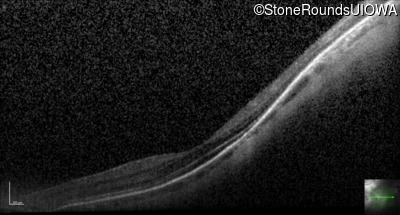

Optical Coherence Tomography - Left - 20/25 +2

Exemplar / OCT Stack